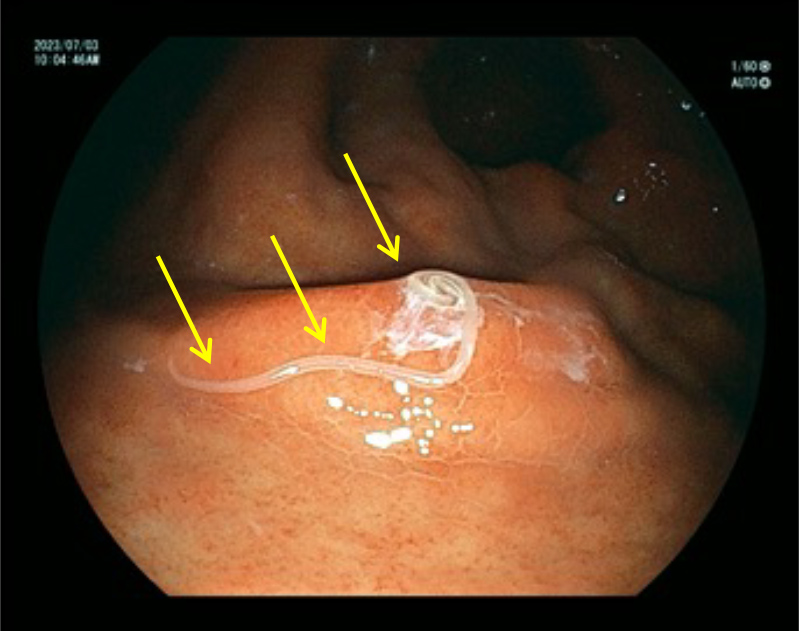

内視鏡検査の所見例

胃体部 胃癌

内視鏡検査の所見例

胃体部 胃癌